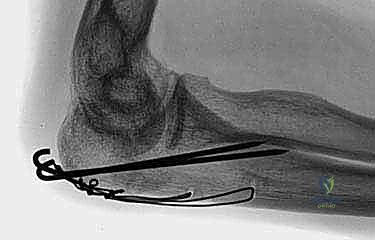

Image

TECH FIG 1 • (continued) C. Two 1-mm Kirschner wires are drilled obliquely across the fracture site so that they exit the anterior ulnar cortex distal to the coronoid process. ( A,B: Copyright David Ring, MD.)

* Retraction: "Once both wires have breached the anterior ulnar cortex, we need to retract them slightly, about 5 to 10 mm. This is in anticipation of later impaction of their proximal ends, ensuring they don't protrude or irritate the soft tissues."